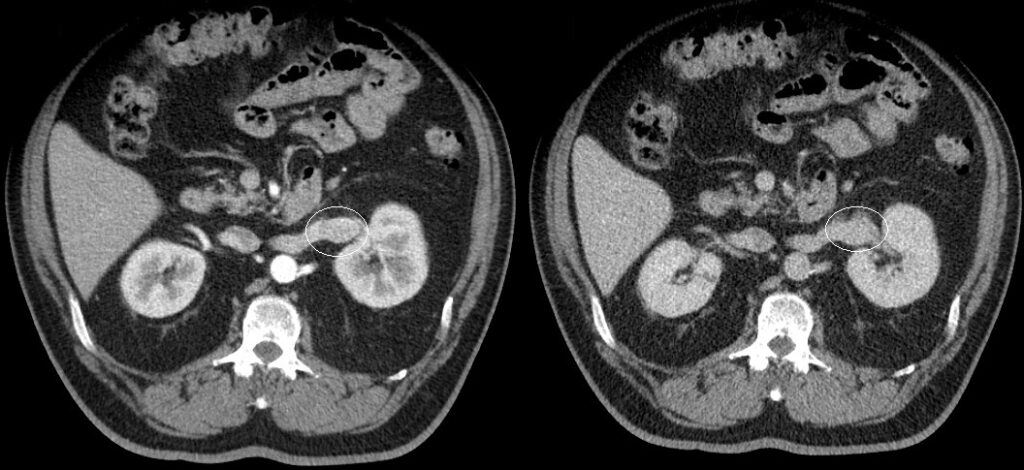

Representa el subtipo más común (70%), se origina a partir de la corteza renal y tiene un componente expansivo. Este tumor tiene un alto contenido de lípidos con áreas de necrosis y focos hemorrágicos, por lo que su característica principal es la heterogeneidad (9); gracias a su amplia red de capilares y vasculatura, con el medio de contraste el realce es evidente en la fase corticomedular de 149 +/- 46 UH, y en la fase excretora con 95 +/- 17 UH aproximadamente 8.

Una vez detectado el tumor se debe proceder a ubicar la extensión del mismo, correlacionándose en un 45% con extensión a la vena renal y metástasis a pulmón, hígado y hueso (2). La tasa de supervivencia a 5 años es del 50% 10 (Fig. 10, Fig. 11).